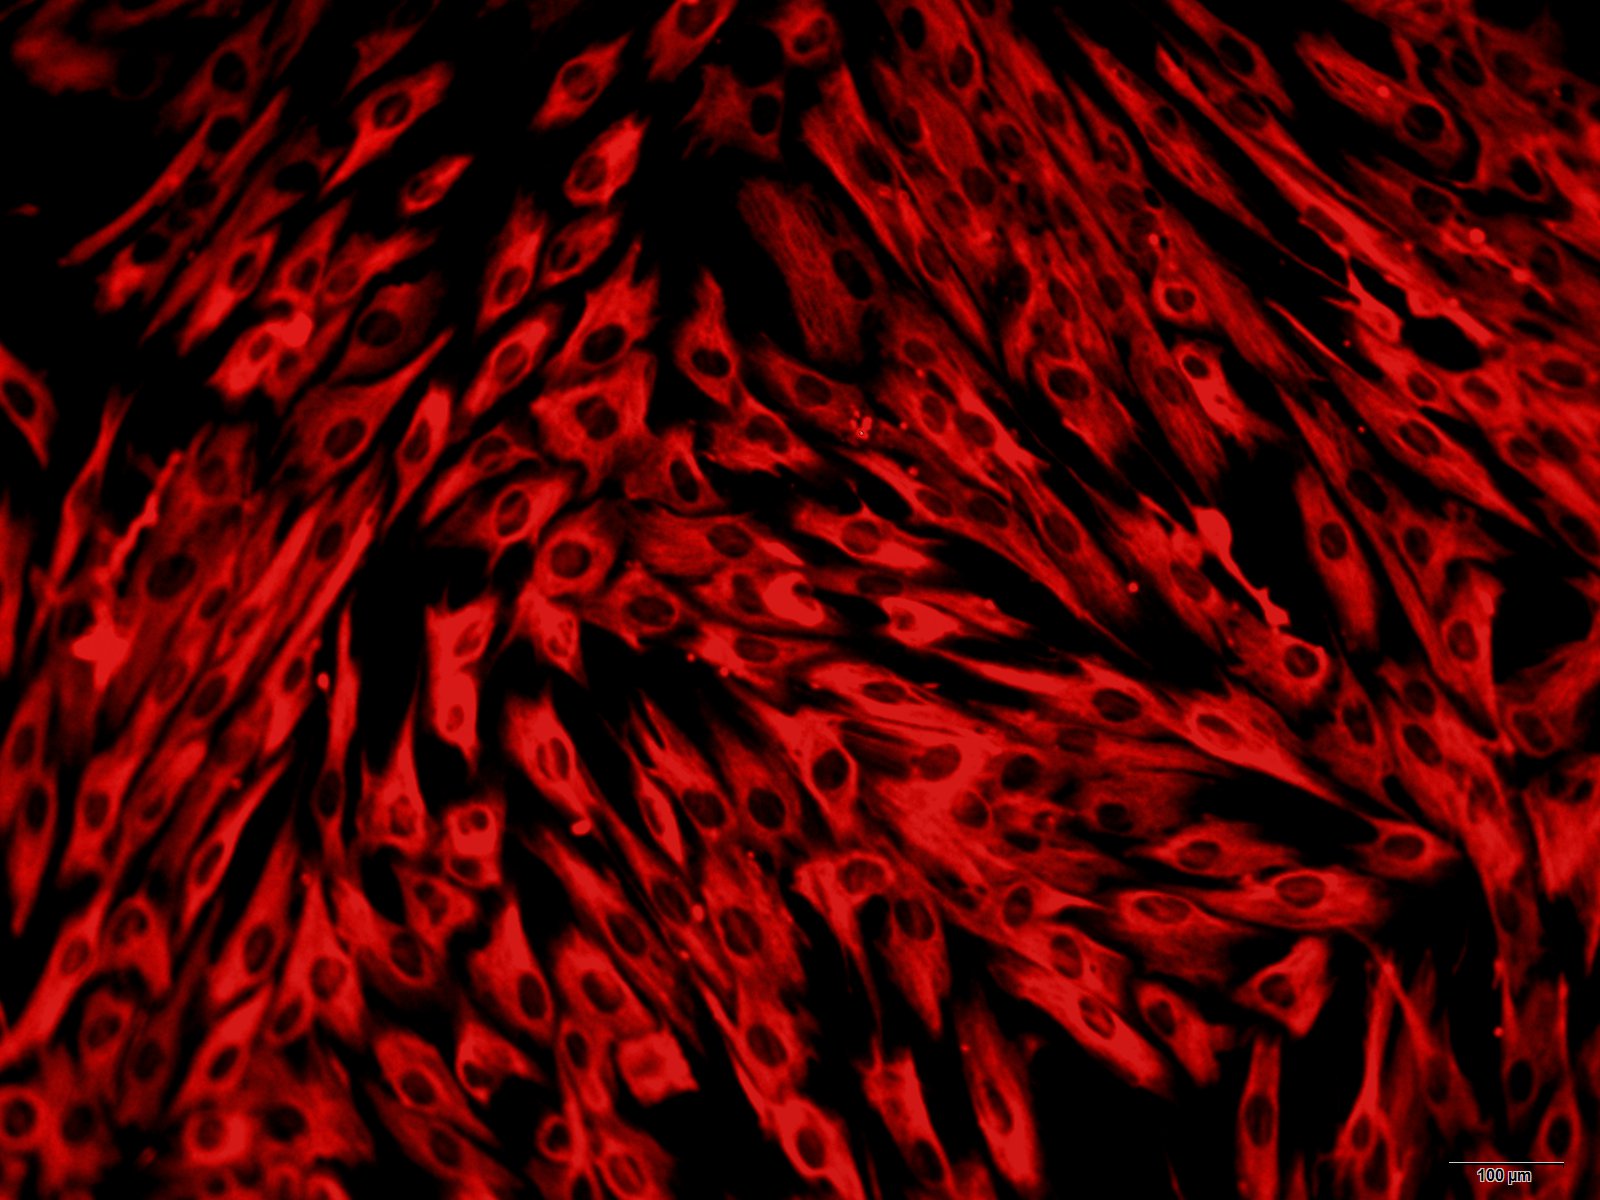

脐带血是胎儿娩出、脐带结扎并离断后残留在胎盘和脐带中的血液,通常是废弃不用的。间充质干细胞(MSC),也被称为间充质基质细胞,是可以分化为一系列不同细胞类型的一种多能细胞,同时有自我更新的能力。研究表明,MSC可以在体外或体内环境下分化为脂肪细胞、软骨细胞、成骨细胞、肌细胞,神经细胞、肝脏细胞和胰岛细胞。

本公司生产的人脐带血基质干细胞采用密度梯度离心法制备而来,细胞总量约为5×105/T25方瓶,细胞纯度可达90%以上,且不含有HIV-1、 HBV、HCV、支原体、细菌、酵母和真菌等。